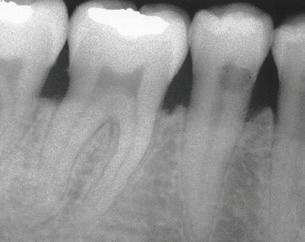

Stage IV –Severe Periodontitis

The American Academy of Periodontology (AAP) released a comprehensive update for the classification and documentation of periodontal and peri-implant diseases and conditions. This comprehensive update was developed and implemented because of the overwhelming information confirming the link between oral health and whole-body health. The first update the dental profession has seen since 1999, the updated classifications include a framework for staging and grading as well as defining the distribution of disease.

The staging consists of the severity of the disease and the complexity for disease management, while the grading defines the rate of progression, a patient’s overall health, social habits, and the expectation of how well the disease will respond to treatment. Distribution expresses if the disease is localized or generalized.

This new classification and documentation of periodontal disease takes into consideration a patient’s current oral condition, health history, and risk factors. This information helps assess how serious an infection in the gingival tissue and underlying bone can be for a patient’s oral health and whole-body health.

THE AMERICAN ACADEMY OF PERIODONTOLOGY UPDATES DISEASE CLASSIFICATIONS

Recognizing and treating periodontal disease in its earliest stages results in better patient outcomes and has been shown to positively affect the long term whole-body health of patients. Early disease recognition and management can only be accomplished by performing a thorough comprehensive exam which includes, but is not limited to, an oral cancer exam, full mouth pocket charting, and radiographs with a clear view of the interdental crestal bone. As clinicians, we know radiographic bone loss, no matter how minor, is a result of a long-standing infection in periodontal tissue.